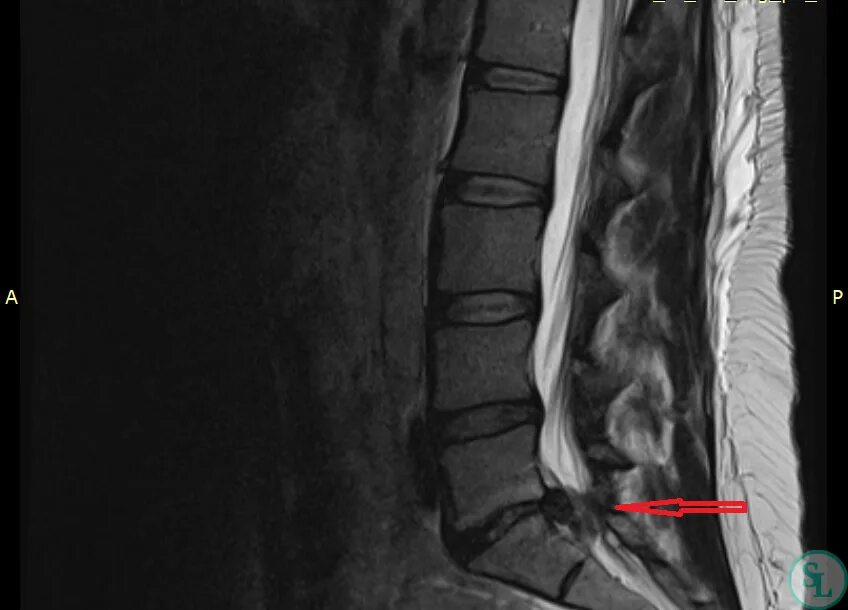

Снижен диск l5 s1